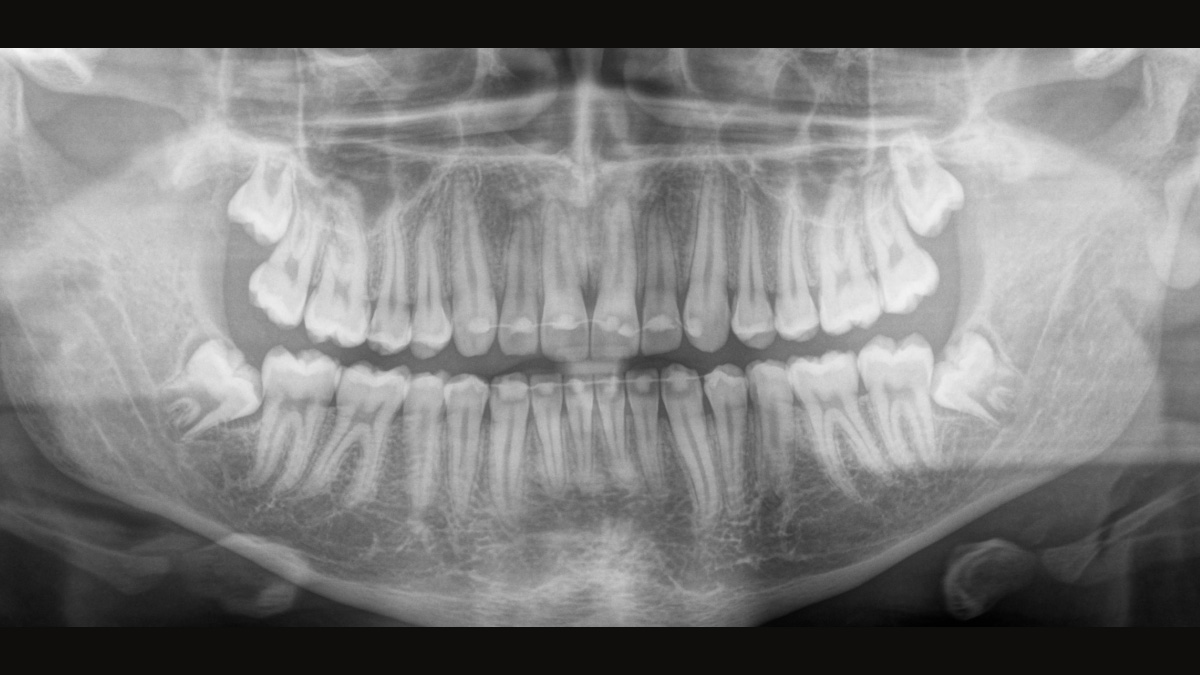

The Direct Conversion Sensor (DCS) has revolutionised the standard of panoramic imaging. X-rays are converted directly into electrical signals. Thus, there is no signal loss due to light conversion, as is the case with conventional systems. The result: images with a high level of sharpness and contrast – even at an extremely low radiation dose. For accurate diagnostic information to support targeted treatment.

The image below shows a panoramic X-ray without and with DCS technology. Using the arrow, drag the control across the image to see the difference the direct conversion sensor makes to the image quality and diagnostic possibilities.

The right focus is crucial for excellent panoramic radiographs. With the autofocus function you will automatically receive an image with the best possible sharpness in focus. Dentsply Sirona Imaging devices take several thousand individual images in one cycle and automatically identify the areas where the jaw is optimally positioned. Without any additional manual steps, these images are then displayed in a final sharp image.

Only some parts of the image are in focus, while other areas are blurred.

The system detects the relevant areas from several thousand individual images in one cycle and automatically identifies the areas where the jaw is optimally positioned.

Sharp images.